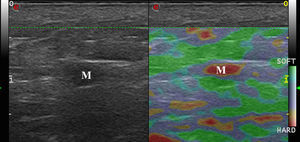

Malignant Skin TumorsElastography shows that malignant skin tumors are stiffer than the surrounding tissue18 (Fig. 5).

Dasgeb et al.25 studied 55 patients with a total of 67 epithelial tumors, of which 29 were malignant (17 basal cell carcinomas and 12 squamous cell carcinomas) and 19 were benign. In this study, the strain ratio was > 3.9 in all malignant skin tumors and < 3 in all benign skin tumors. For strain ratio values between 3.00 and 3.9, sensitivity and specificity were 100% in the diagnosis of malignant lesions.

Elastography has been used to study melanoma. In a pilot study by Botar et al.,26 42 melanomas in 39 patients were studied using SE and color Doppler ultrasound to assess vascularization.

The melanomas were hypervascularized and had multiple vascular pedicles, and SE showed that the lesions were stiffer than the adjacent skin. The lesions with the highest degree of vascularization had the greatest stiffness.

The correlation between melanoma neovascularization and prognosis is well known in the literature.27,28 Therefore, lesion stiffness could be a prognostic factor in melanoma.29